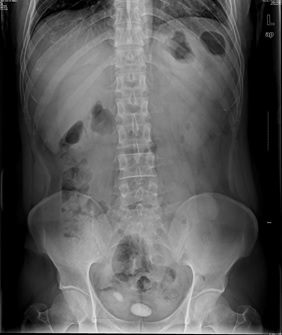

05卷-4.男,55歲,反復(fù)尿頻、尿痛、排尿困難半年(本題滿分2.00分)

A.膀胱癌

B.膀胱結(jié)石

C.前尿道結(jié)石

D.前列腺肥大

本題答案:B

題目解析:【該題針對“X線-泌尿系結(jié)石”知識點(diǎn)進(jìn)行考核】